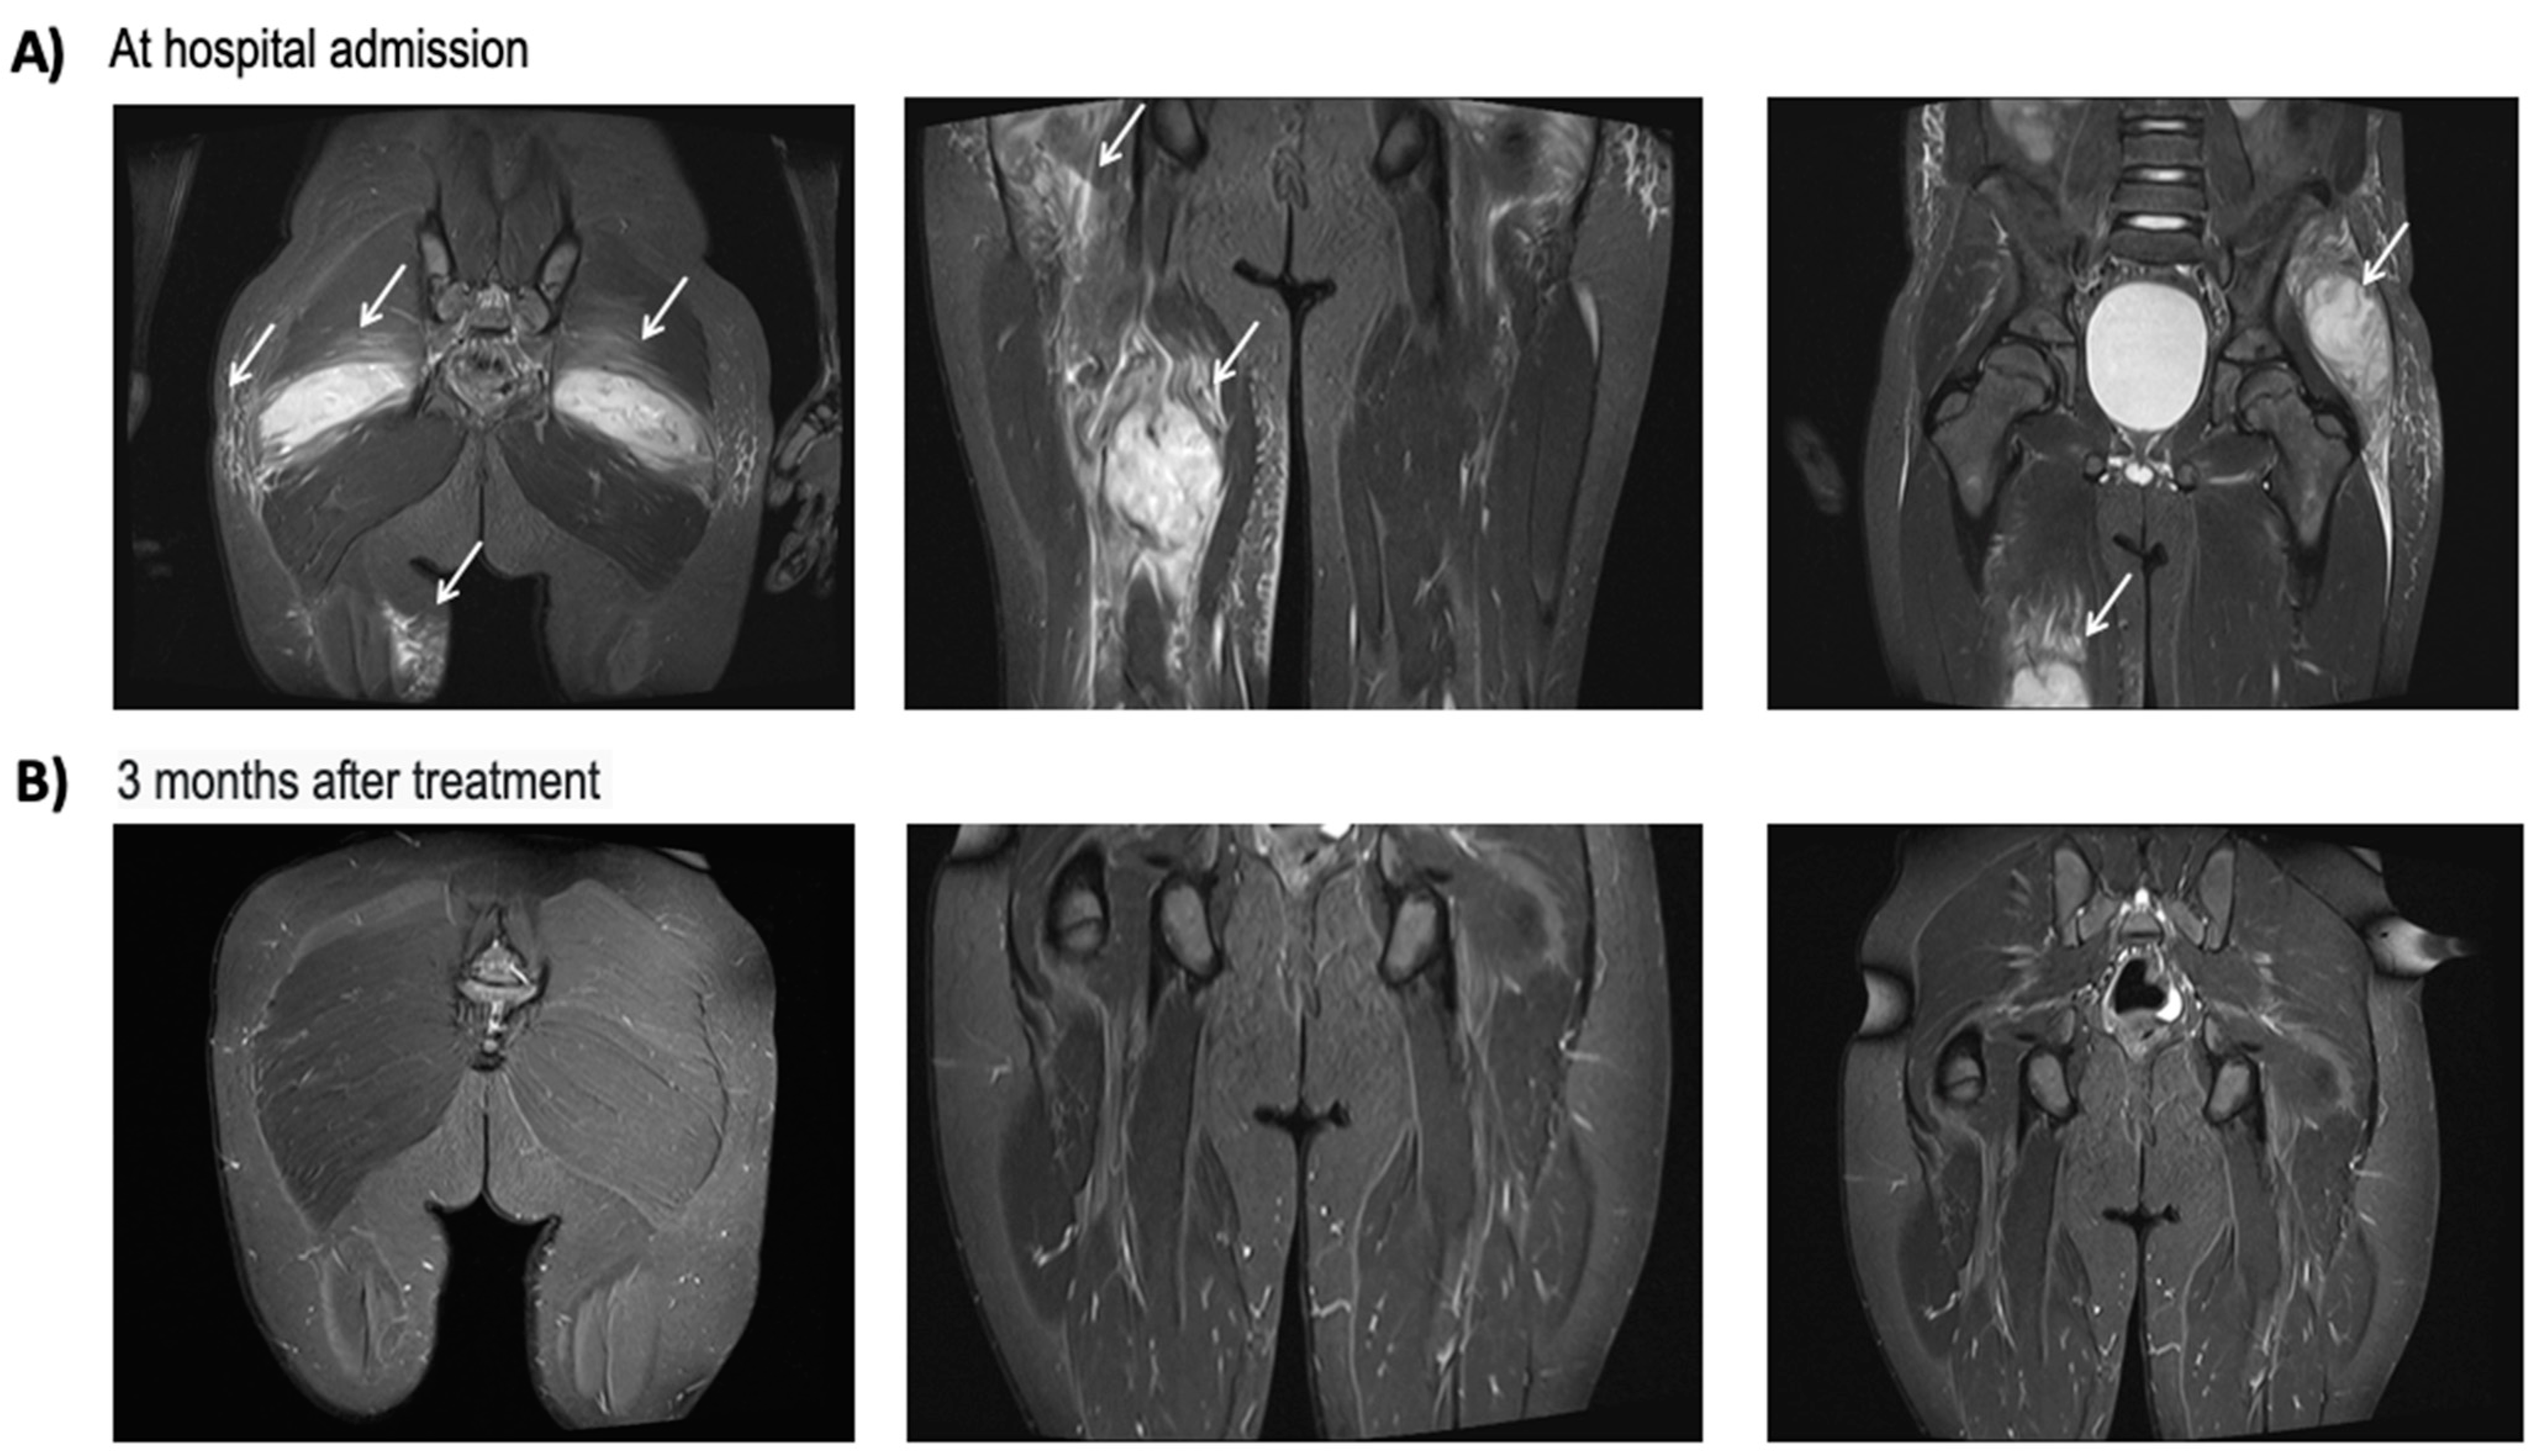

2.2. Patient #2